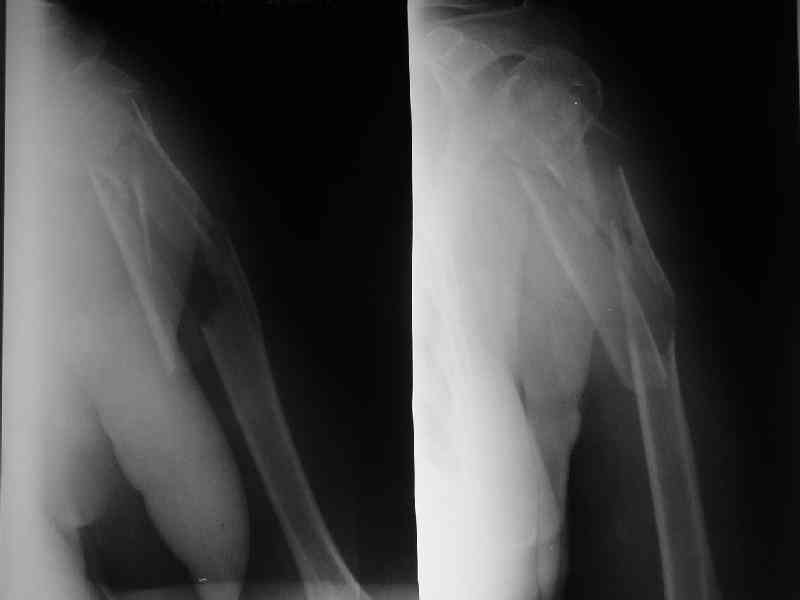

Здесь нет необходимости в серкляже. Вмешиваться на промежуточных

отломках приходится, если есть угроза перфорации кожи, или

промежуточный отломок попал в фасцию, как пуговица в петлю. В

приложении сегментарный оскольчатый перелом плеча в проксимальном

отделе, фиксированный больщеберцовым стержнем. Как видите, обошлось

без серкляжа. Функция полная.